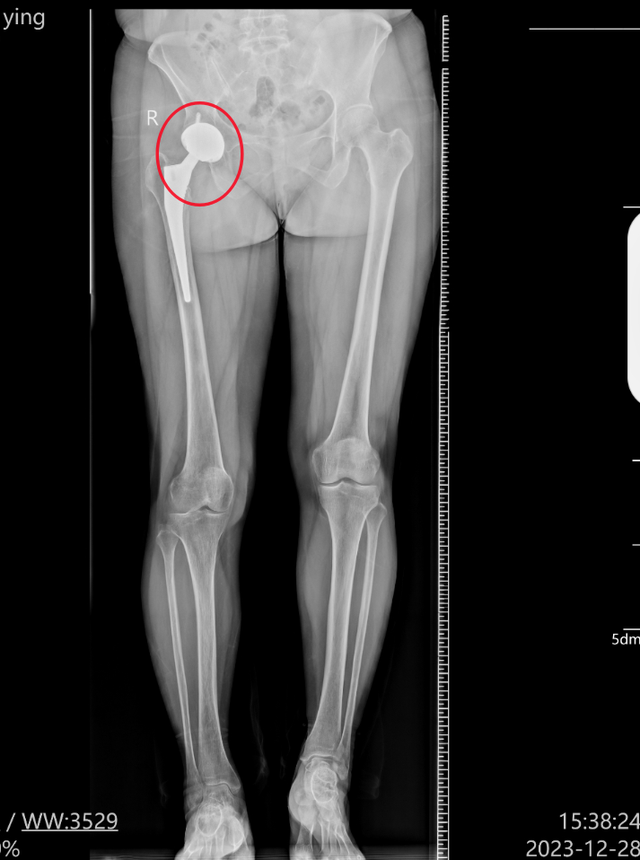

2023年8月28日,任女士到湖北民族大学附属民大医院做检查,结果显示双下肢不等长。

该医院的一份关于她的门诊病历显示,体格检查“右下肢较对侧长约2厘米。”

此外,在过错和原因力等方面,江西求实司法鉴定中心出具的一份《司法鉴定意见书》称,针对任女士的实际情况,医方予以右侧全髋关节置换手术方案系选择不当,且手术知情同意书中手术方案及替代方案空缺,术前亦未告知患者术后下肢不等长风险,医方未尽到一般注意义务和充分的告知义务,存在过错。结合术后影像学资料,任女士术后下肢不等长考虑与其右侧假体颈过长有关,医方术中未尽到高度注意义务,亦存在过错。最终认定来凤县中医院为任女士提供的诊疗行为存在过错,过错与她的损害后果之间存在因果关系,系同等原因(建议过错参与度为45%-55%)。

该人士进一步介绍说,髋关节置换手术中,术后双下肢长度差异是关键性的手术目标,但完全避免差异具有一定挑战性,一般来说小于或等于1厘米被认为是临床的可接受范围,多数患者可良好耐受,无需干预,如果大于1厘米,可能引发诸如跛行、下腰疼痛或假体松动等症状,最理想的差异是努力控制在0.5厘米以下,如果差异大于2厘米通常需要鞋垫调整或做翻修手术。手术之前医生应通过影像学(X线、CT)精确测量健侧与患侧下肢长度,制定个性化截骨和假体安置方案,手术过程中应使用定位导板、计算机导航或机器人辅助技术提高精度,通过试模复位后直接测量或透视确认下肢长度,“根据任女士的实际情况看,她术后下肢不等长考虑与其右侧假体颈过长有关,医生在手术过程中未尽到高度的注意义务,存在相应的过错,而这种结果是比较少见的。”